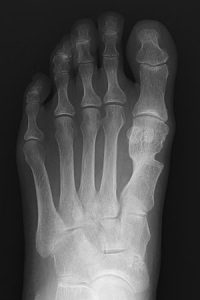

外反母趾

検査、診断

- 外見からも診断できますが、重症度を見るために、レントゲン、CT等を行います

- レントゲンで第1中足骨と第1基節骨のなす角を外反母趾角と称し、15度までを正常、15-30度を軽度、30-40度を中等度、40度以上を重度としています。

- 第1中足骨、第2中足骨のなす角度、M1M2 は10度までを正常としています。

- 変形が強いと2番目の足の指の上に母趾が乗ることもあります